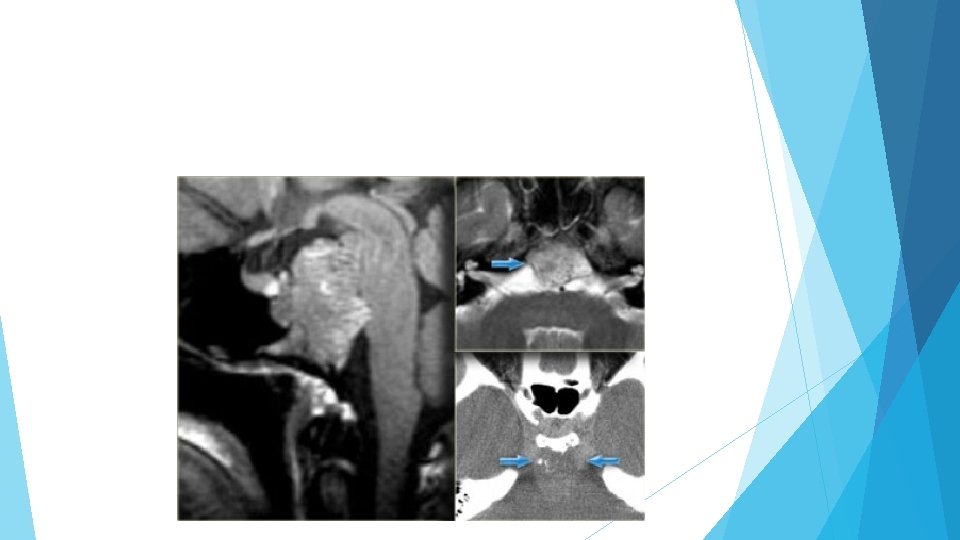

Cavernous sinus invasion It is not always possible to tell if there is cavernous sinus invasion, but there are three signs to look out for: -Is there more than 50% encirclement of the carotid artery? Note: meningiomas tend to constrict the carotid artery, macroadenomas do not. -Is there lateral displacement of the lateral wall of the cavernous sinus compared to the opposite side? -Is there an increased amount of tissue interposed between the carotid artery and the lateral wall of the cavernous sinus?

On the top-left unenhanced and enhanced CT-images, the main differential diagnosis of the enhancing mass would include meningioma, pituitary adenoma and an aneurysm. The post-constrast MR-image on the top-right rules out an aneurysm as a possible diagnosis (no flow void), but on axial images a pituitary adenoma and meningioma are still difficult to differentiate

Notice the spread of the lesion along the meninges. The epicentre of the lesion is above the sella.

Note the compresses pituitary gland There is no evidence of cystic change or hemorrhage